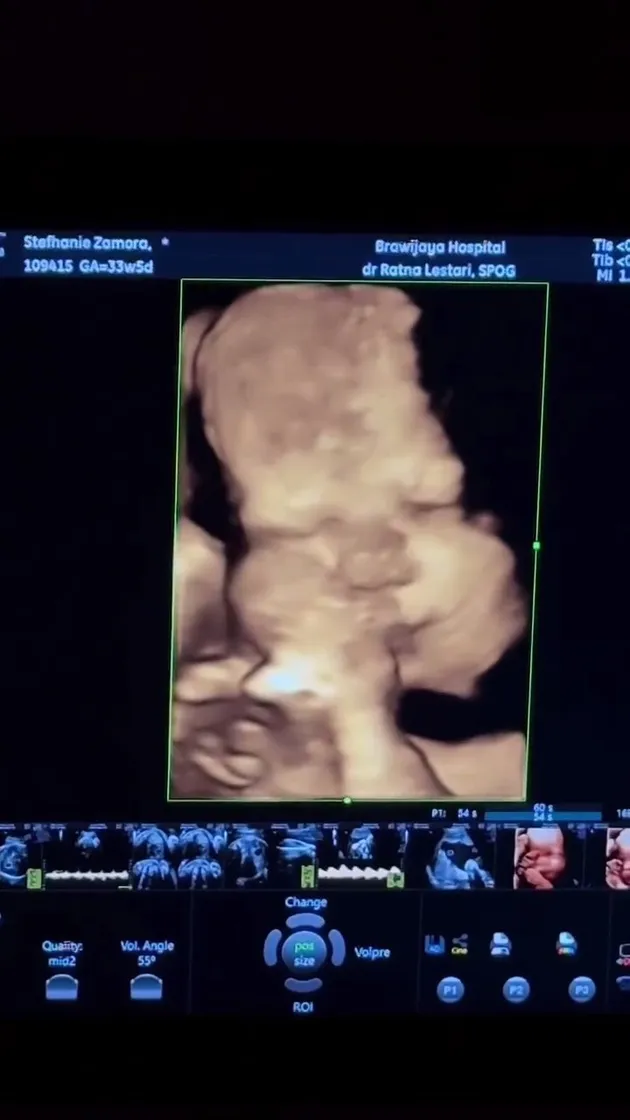

Steffi Zamora once again captured public attention through a special moment ahead of the birth of her first child with Nino Fernandez. Through a post on social media, Steffi showcased a moment of herself undergoing an ultrasound examination in the third trimester of her pregnancy.

In the photos shared, Steffi appears to be smiling happily as she looks at the ultrasound results showing the face of her future child. Here are the moments of the artist.